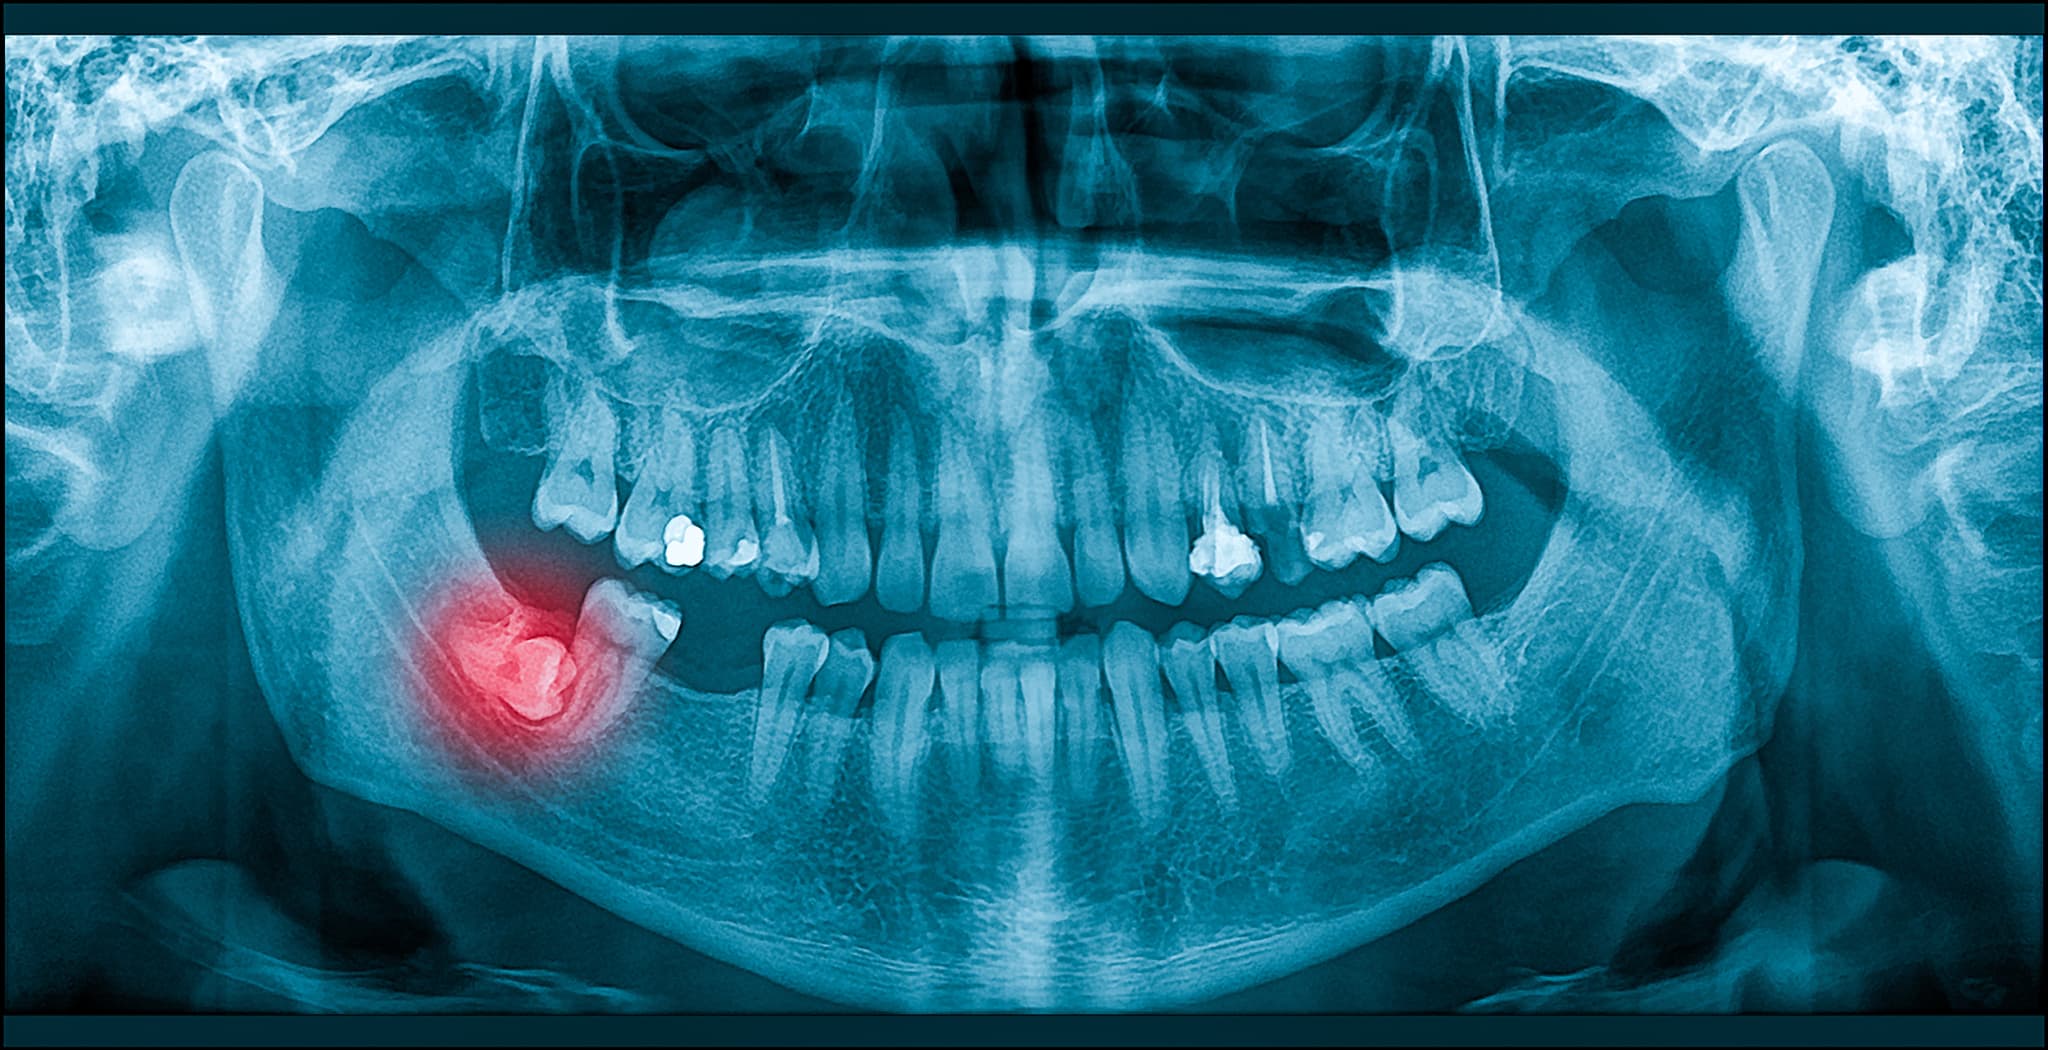

嚢胞が形成される

横向きに生えた親知らずを放置すると、嚢胞(のうほう)が形成されることもあります。嚢胞とは、液体や膿が溜まった袋状の病変のことです。嚢胞が小さいうちは特に問題はありませんが、大きくなると周囲の骨を溶かしたり、重い感染症につながったりするリスクもあります。